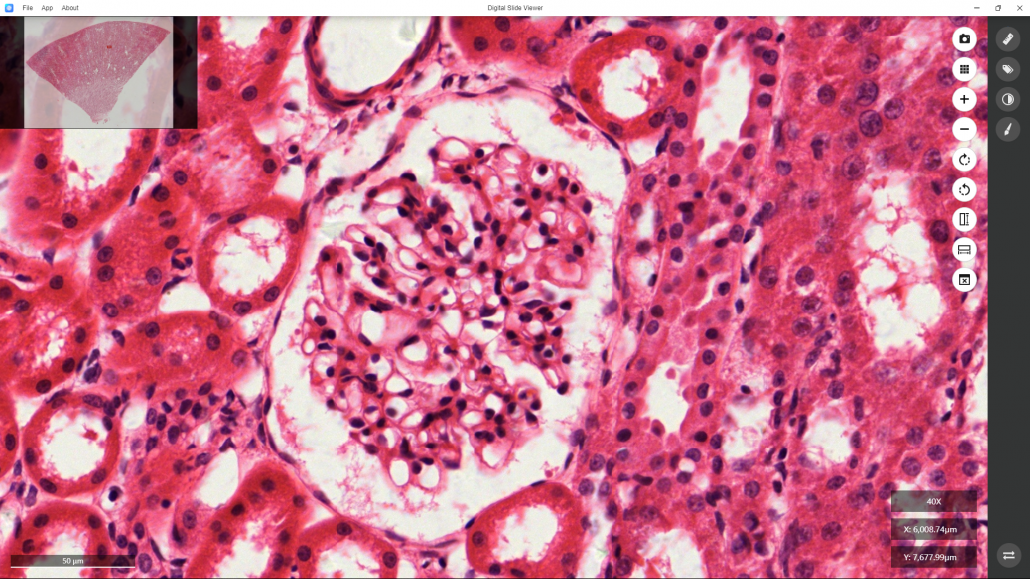

Here, for example, you want to observe the detailed structure of a glomerulus in this section. You may lock on the target and continue to enlarge the image in the same way as described above.

At this highest magnification, indicated by “40X” (objective lens) shown at the bottom right corner, a clear image of glomerulus appears at the center.